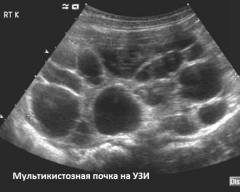

| Мультикистозная дисплазия почек | Обнаружение кист и одностороннего поражения. | Увеличение почки с множеством эхонегативных образований. |

| Мультикистозная дисплазия почек | 1. Определение количества и расположения кист. 2. Выявление одностороннего поражения почек. | На УЗИ наблюдается одностороннее увеличение почки с множеством эхонегативных образований различного диаметра. Эхогенность почечной ткани между кистами неоднородна. |